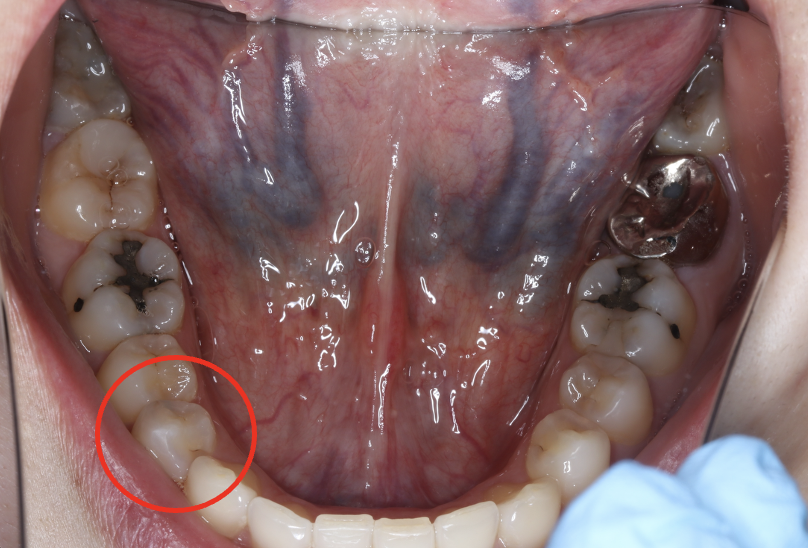

セラミック症例④

年齢50代男性

治療期間1ヶ月

治療内容セラミックインレー、クラウン

治療箇所

左下7番 左上4番、5番、7番 右下6番 右上5番

治療費用600,000円